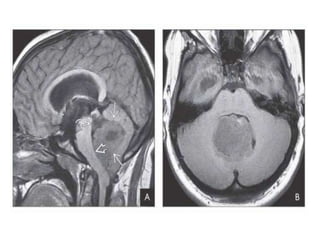

T1WI in a 57-year-old woman with headaches, intermittent visual problems shows well-

delineated,slightly hypointense mass in the pineal gland. T2WI shows that the mass is

heterogeneously hyperintense with some areas of cystic degeneration .

Moderate heterogeneous enhancement is seen on T1 C+. MRS shows elevated Cho , decreased

NAA , lactate doublet . Pineal parenchymal tumor of intermediate differentiation, WHO grade

II, was diagnosed on imaging and confirmed at histopathology